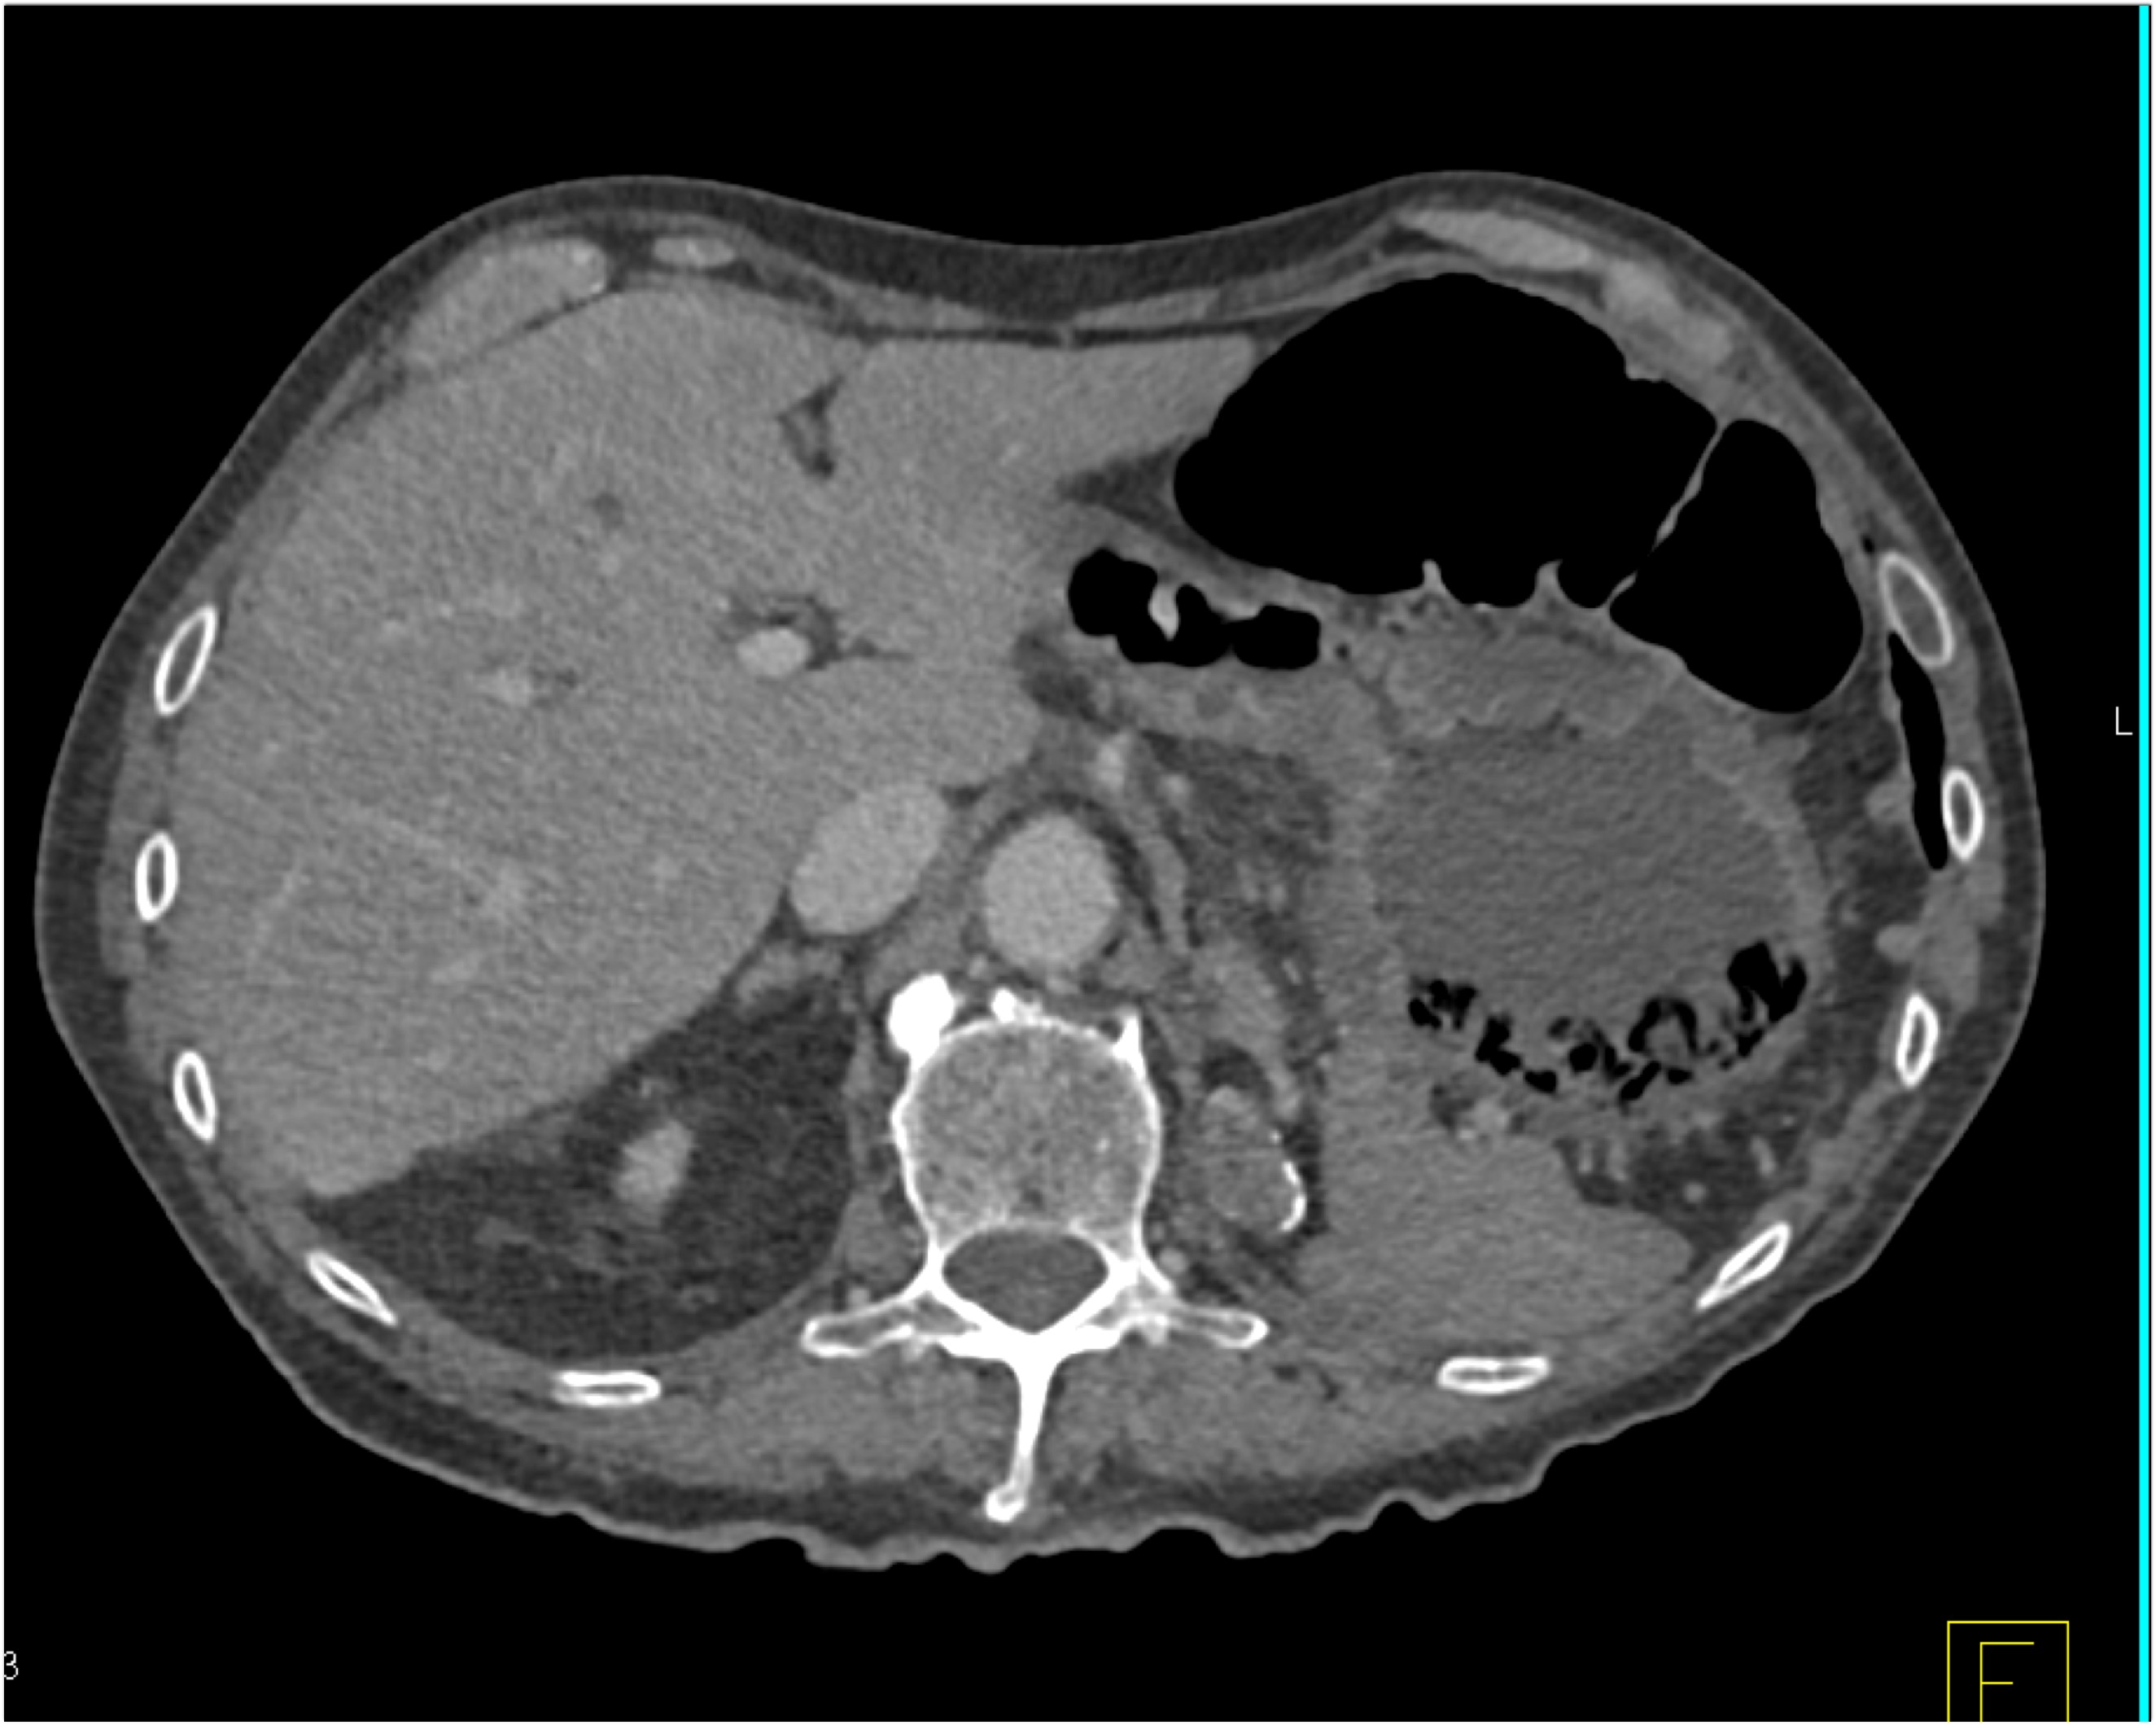

8) The most likely diagnosis in this case is?

clear cell renal cell carcinoma

large B-cell lymphoma

seminoma

renal abscess